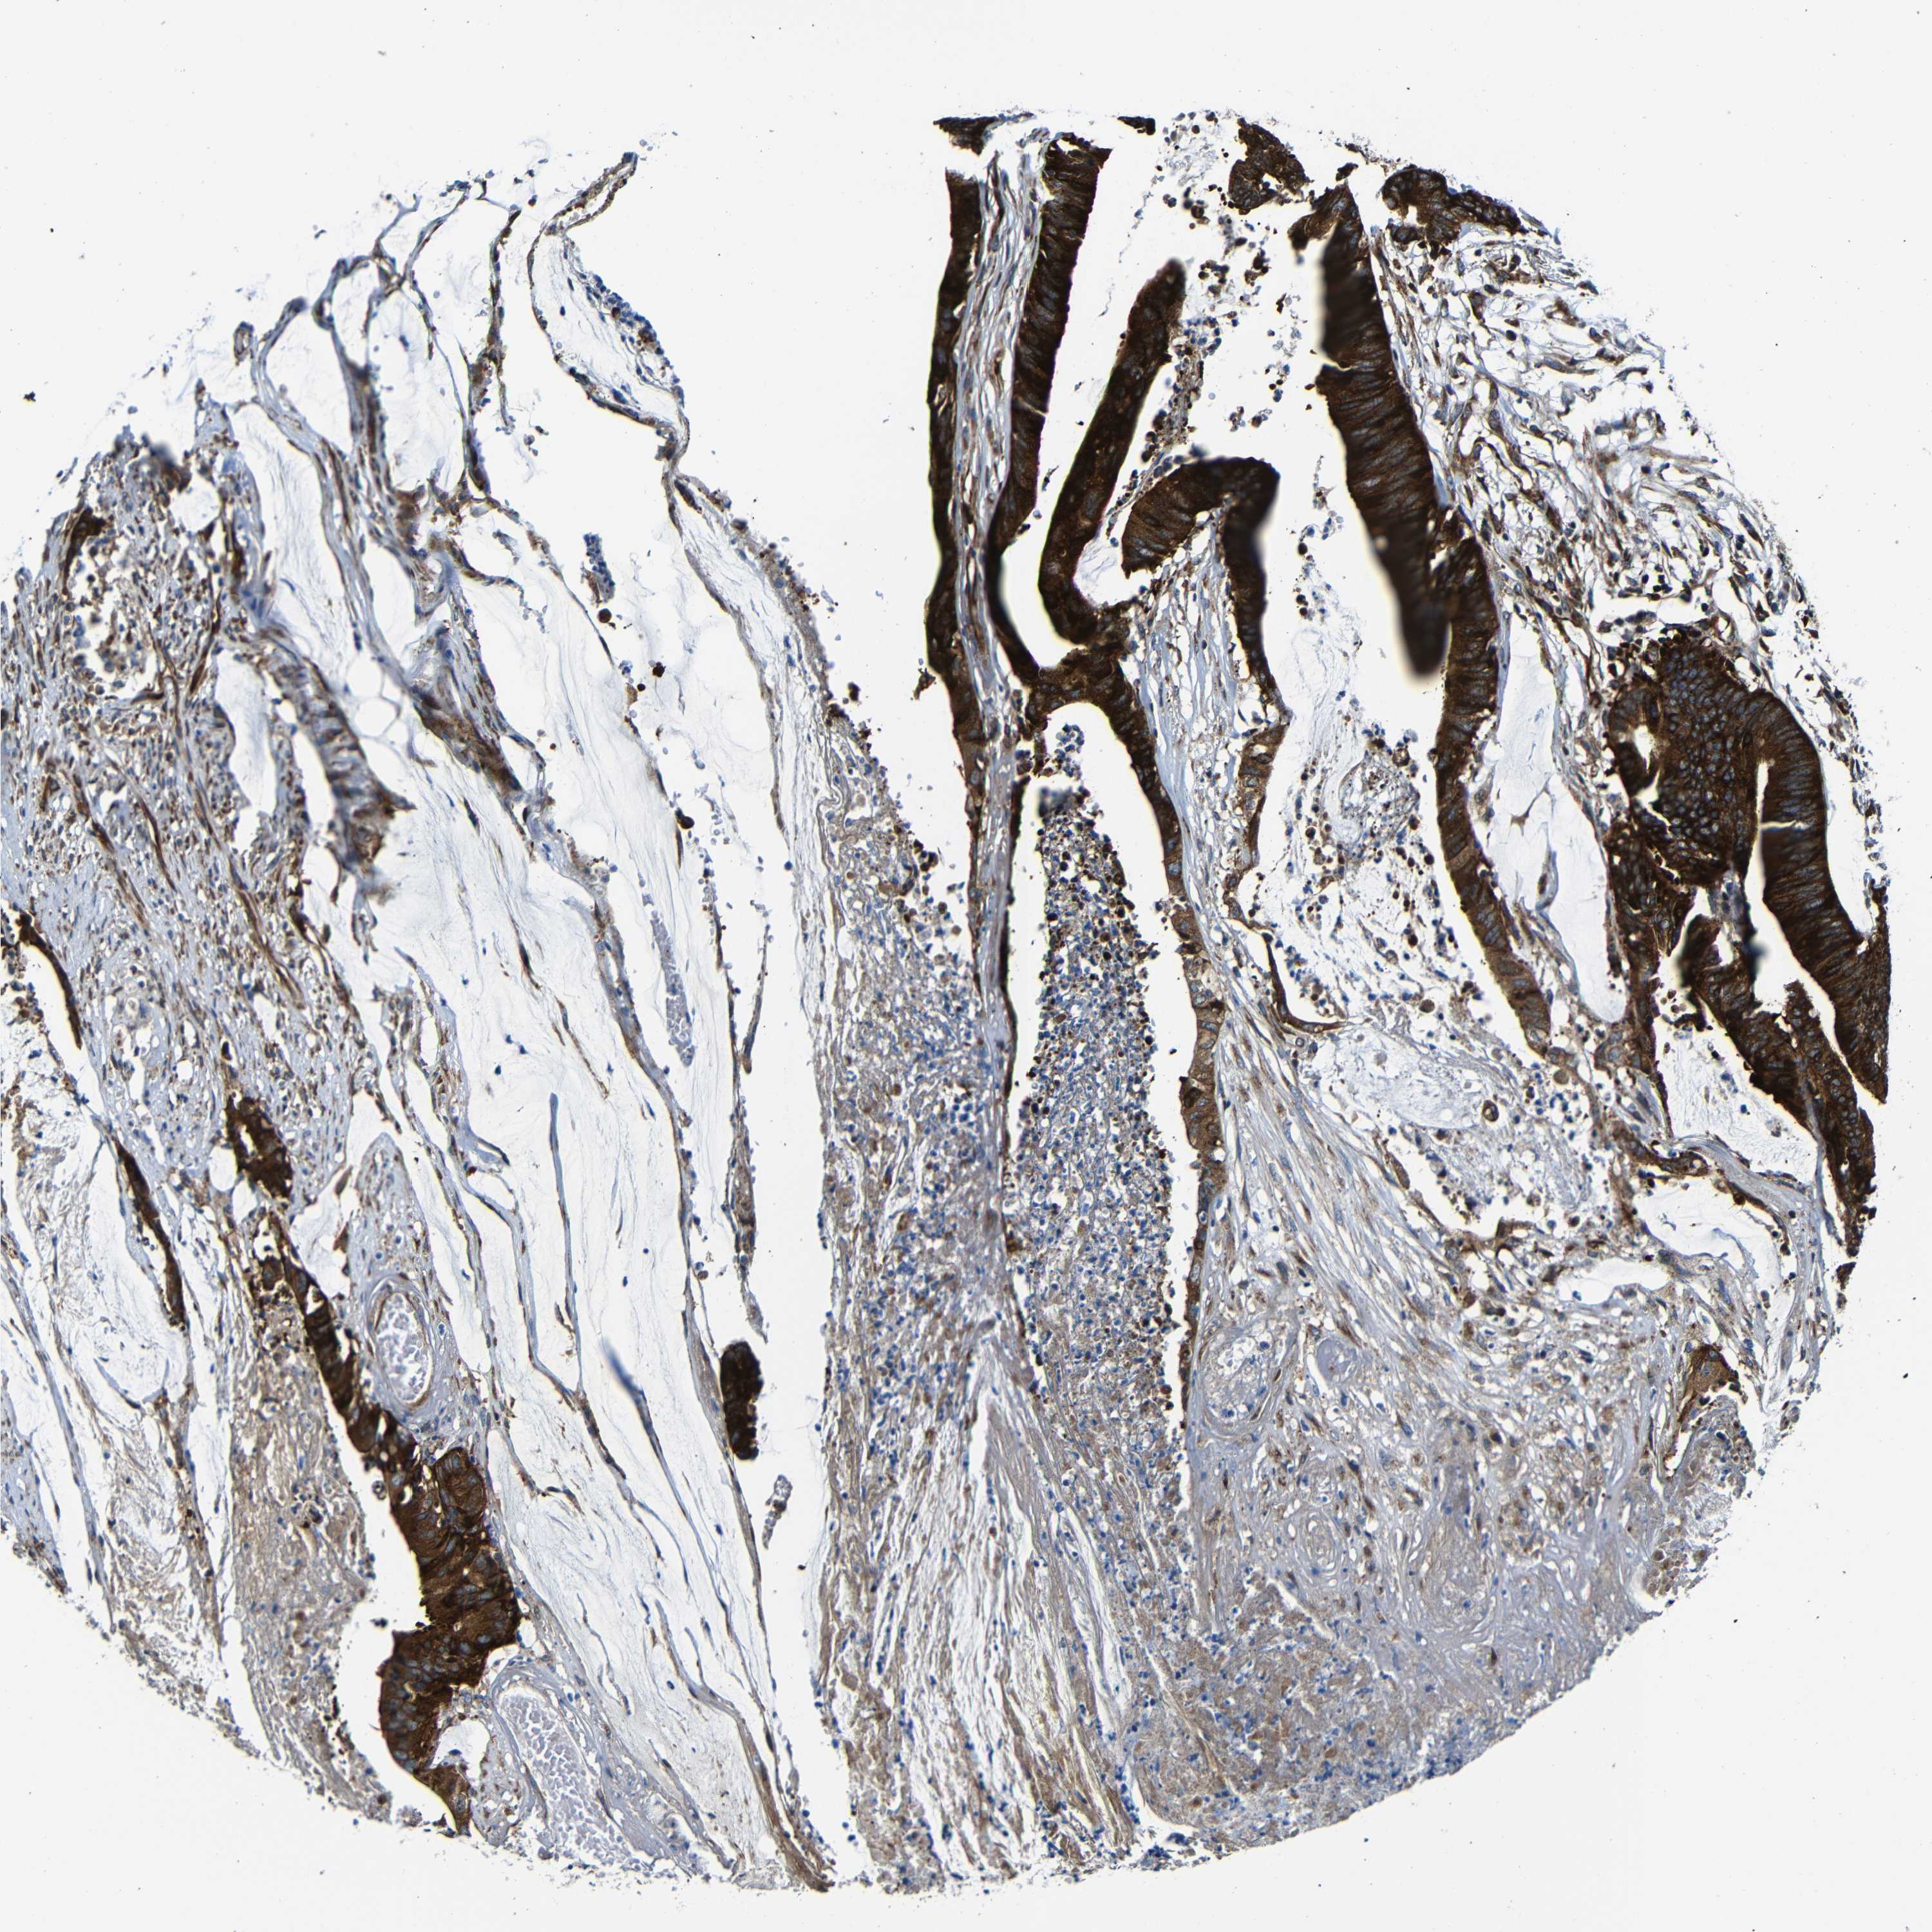

CANCER COLORECTAL CANCER Show tissue menu

Colorectal cancer

Human cancer

Colon adenocarcinoma